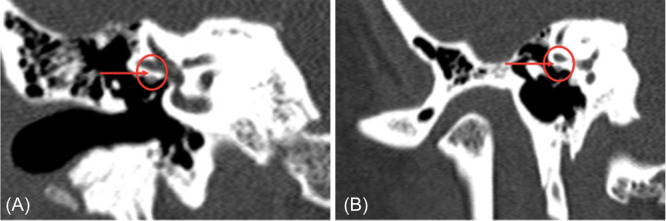

Methods: We measured the bony partition thickness between the FC-LSCC in human temporal bone otopathological specimens and CT scans. The clinical study involved a series of reviews of patients with FC-LSCC, presenting clinical data and CT images.

Results: The average thickness of the bony partition measured via CT was 0.6 mm ± 0.2 mm, whereas in otopathological specimens it was 0.56 mm ± 0.17 mm. We identified 34 patients with FC-LSCC dehiscence. The most frequently reported symptoms were hearing loss (44%), dizziness/vertigo (44%), and tinnitus (41%). Of the patients, 15 (44%) had more than 1 site of bone dehiscence and 21 (62%) had bilateral FC-LSCC dehiscence. We then identified 36 patients in whom only FC-LSCC dehiscences were found and provided characteristics for this population.